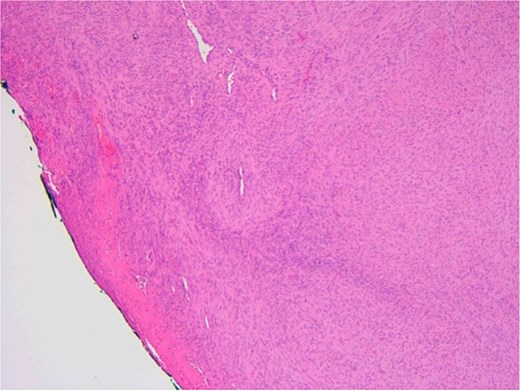

The patient underwent a biopsy of the lesion. Histopathological analysis revealed spindle cell proliferation arranged in a fascicular growth pattern, dilated hemangiopericytoma-like vessels, and a central myeloid nodule. Immunohistochemical staining was positive for smooth muscle actin (SMA), with no evidence of cellular atypia (Figs 5–7).

Oral squamous mucosa with underlying bland spindle cell proliferation showing fascicular growth and dilated haemangiopericytoma-like vessels and a myoid nodule centrally.